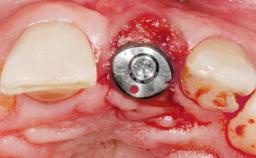

Late Placement of an Implant in a Maxillary Left Central Incisor Site

Type of Implants Two-Piece

Bone Augmentation Horizontal|Staged

Augmentation Materials Xenogenous|Membrane

Placement Protocol Early or late implant placement